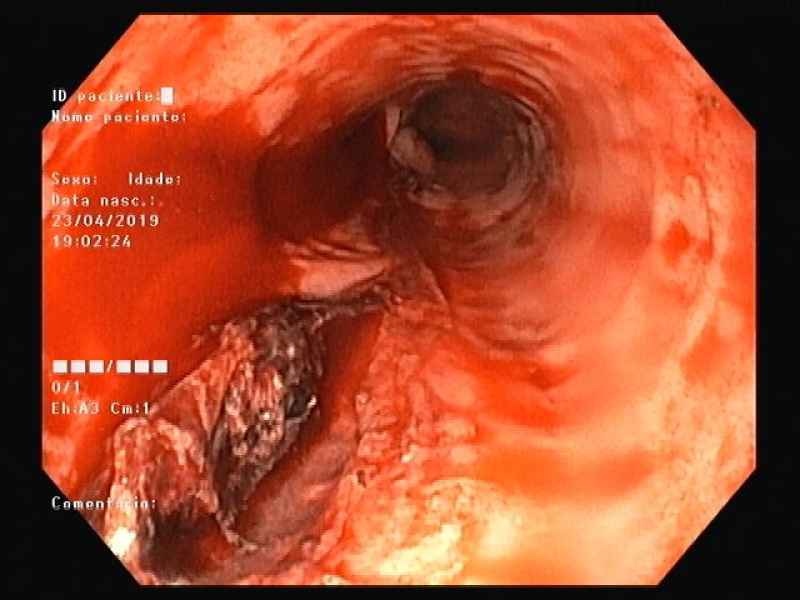

Behind an adherent clot

Fotografia